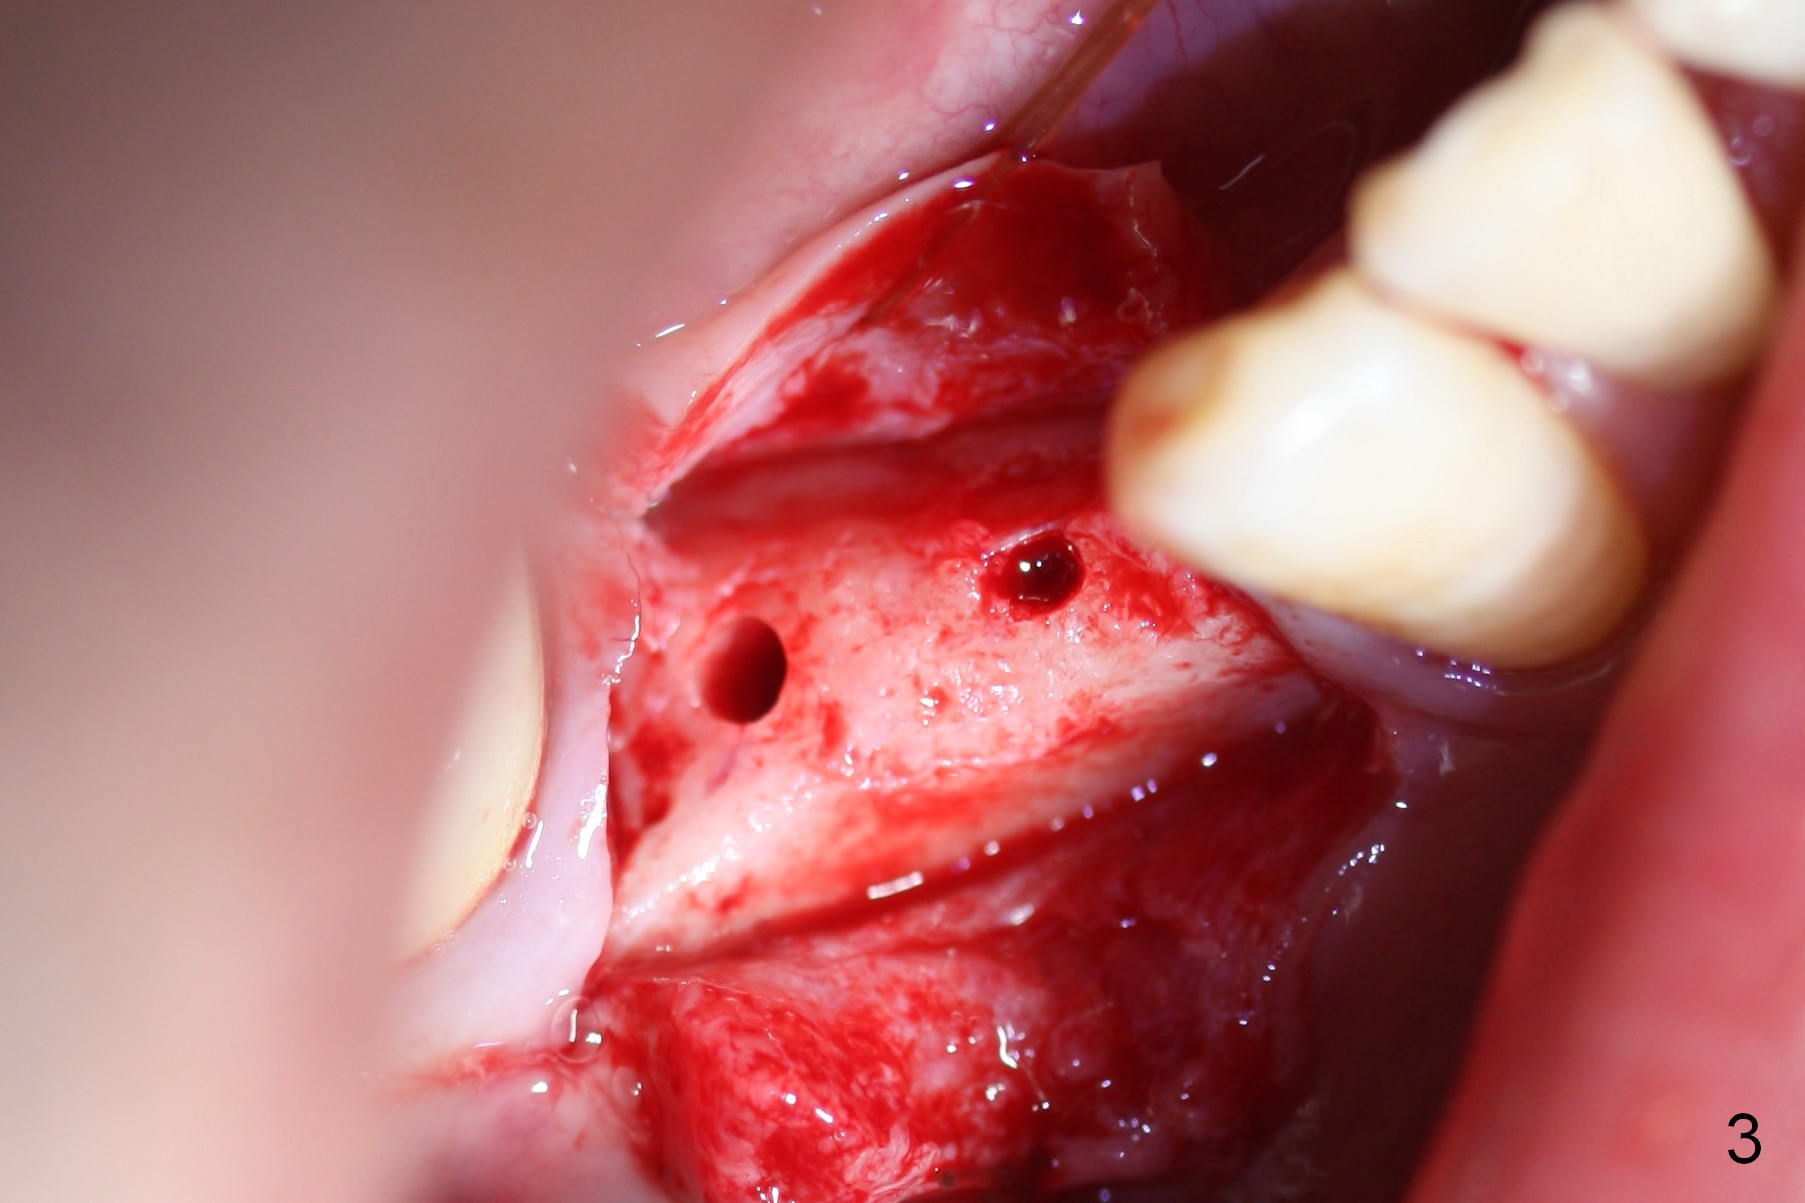

The patient has lost several teeth, which are replaced by removable partial dentures. He wants to have implants in the lower right first because of loss of a buccal clasp over the tooth #30 (Fig.1). When the lower partial is removed, a narrow soft tissue band is visible in the edentulous area. The hard tissue ridge is approximately 3 and 5 mm buccolingually at the sites of #28 and 29, respectively (Fig.3 after initial osteotomy). To place 2 adjoining implants at the same level, the treatment plan is modified: a 3 mm 1-piece implant will be placed at #28, while the plan at #29 remains the same: a 4.5 mm 2-piece implant.